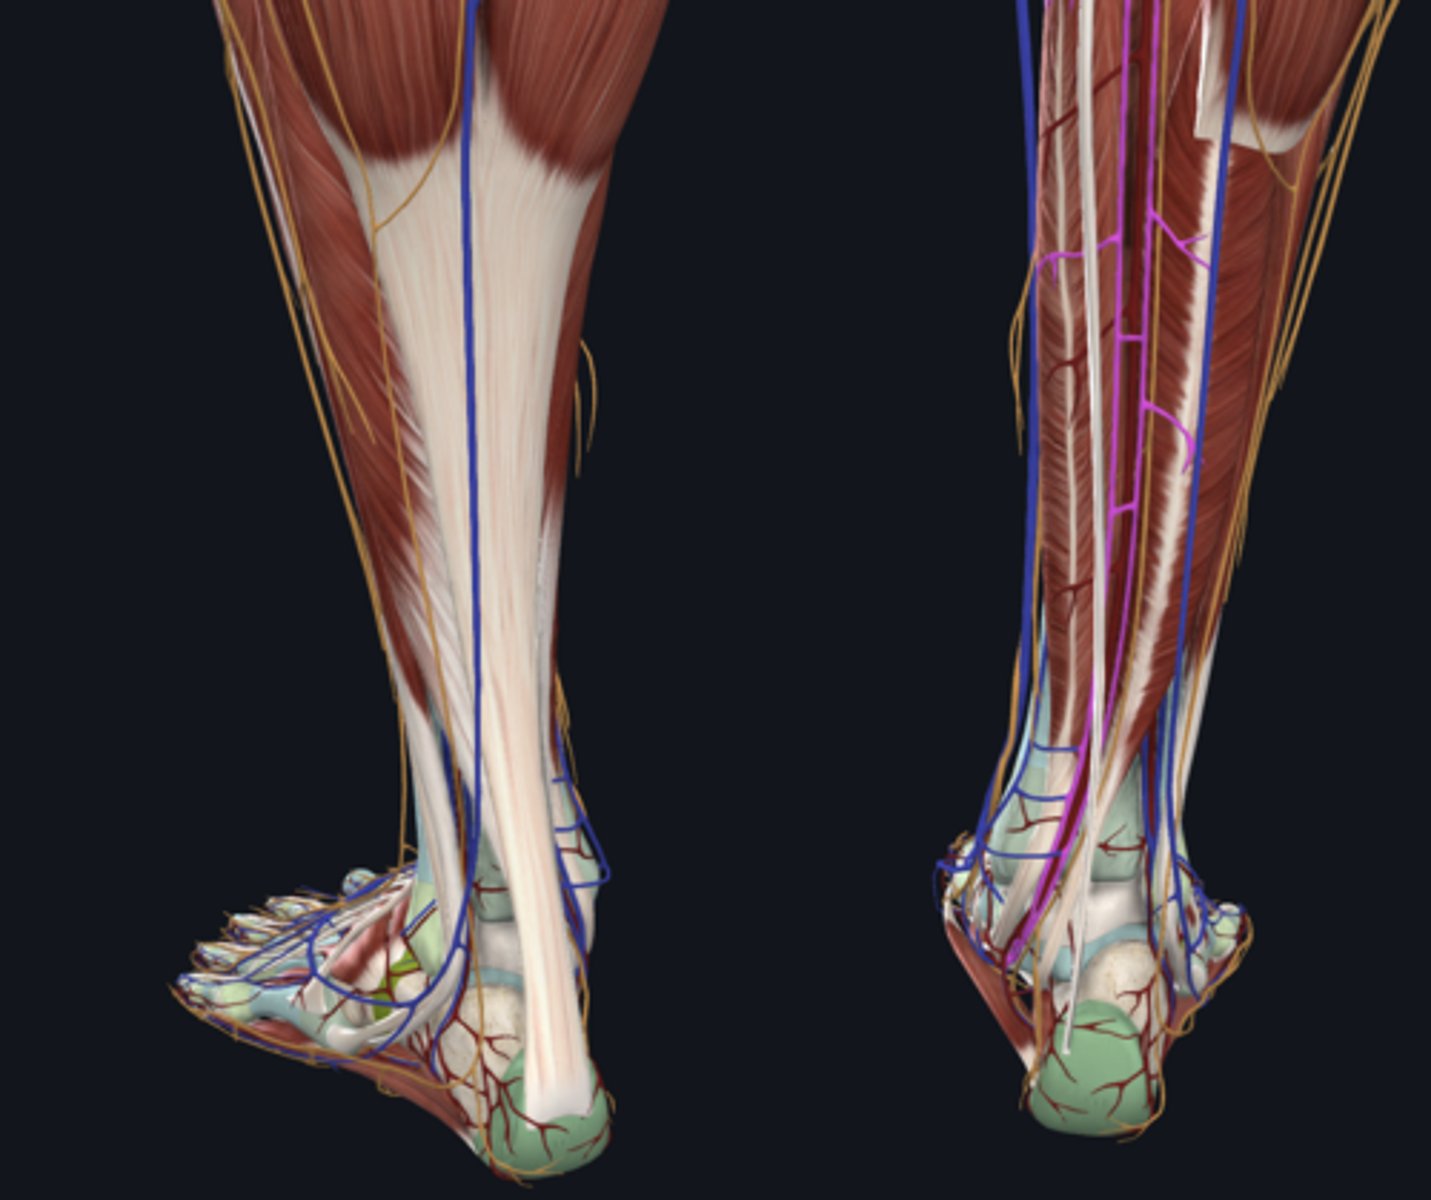

Popliteal artery

artery

Popliteal vein

vein

Tibial nerve

nerve

Medial head of gastrocnemius

Lateral head of gastrocnemius

Soleus

Plantaris

Flexor digitorum longus

tendon in tarsal tunnel

Flexor hallucis longus

tendon in tarsal tunnel

Tibialis posterior

tendon in tarsal tunnel

Tibial nerve (in tarsal tunnel)

nerve

Posterior tibial artery (in tarsal tunnel)

artery

Posterior tibial vein (in tarsal tunnel)

vein

Great saphenous vein

vein